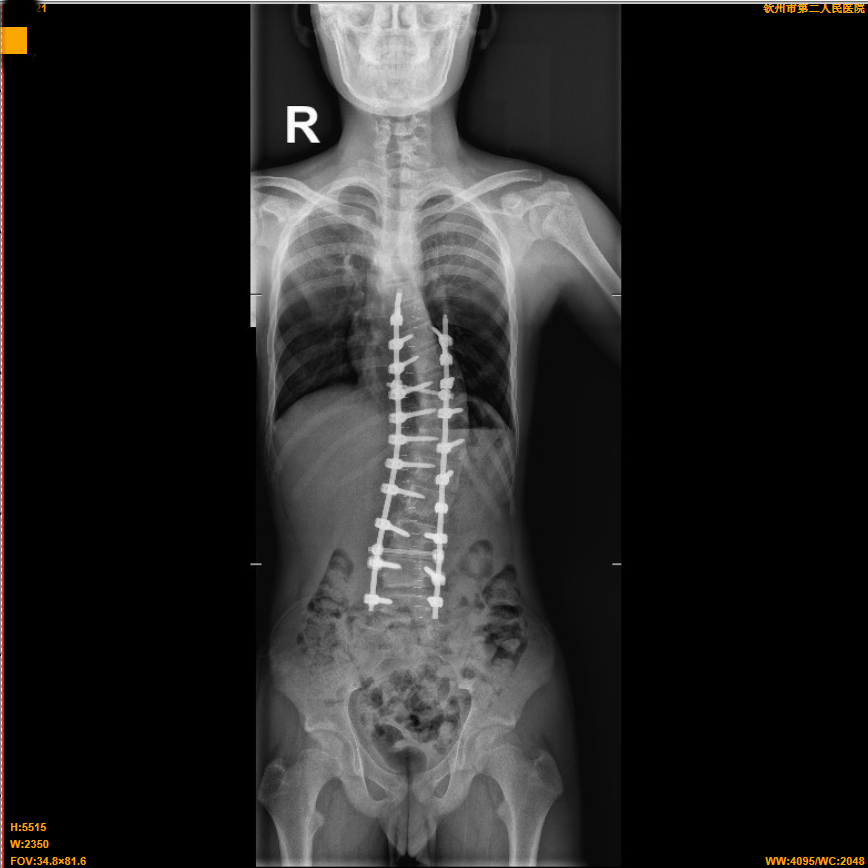

近日,我院脊髓脊柱外科(骨外科三区)成功为一名13岁的青少年小明(化名)成功实施特发性脊柱侧弯矫正手术。术后身高从原来的158cm增高至164cm。该手术的成功施行标志着我院脊髓脊柱外科手术水平又迈上了一个新台阶。

入院骨外科三区(脊髓脊柱外科)后,立即给予完善相关检查,检查结果排除了先天性骨结构异常、脊髓神经等疾病所致脊柱侧弯。结果提示小明患的是:特发性脊柱侧弯!

为了给予小明及时,最优、个性化的治疗,骨外科三区(脊髓脊柱外科)专家团队结合检查结果对小明的病情进行详细的分析和讨论,明确手术方式和手术部位,并与团队提前做好各项术前准备,最终确定为特发性脊柱侧弯矫正手术,手术由仇继任主任医师、罗坤烈副主任医师等专家为小明开展。术中,经过精密计算,成功将小明的脊柱进行了矫正,使其身体恢复了平衡,术后2天,小明已经可以在胸腰椎支具固定下进行下床活动并逐步进行功能锻炼。术后测量,小明的身高也从原来的158cm增高至164cm,患者及其家属对手术效果非常满意。目前,患者恢复良好,已经顺利出院,出院时身体平衡稳定。

脊柱侧弯也叫做脊柱侧凸,指的是脊柱的一个或数个节段在冠状面、矢状面和水平面上的序列异常,是一种脊柱的三维畸形。通俗来说,正常人的脊柱从后面看是直的,而脊柱侧弯患者的脊柱从正面看是呈字母“C”形或者“S”形的。